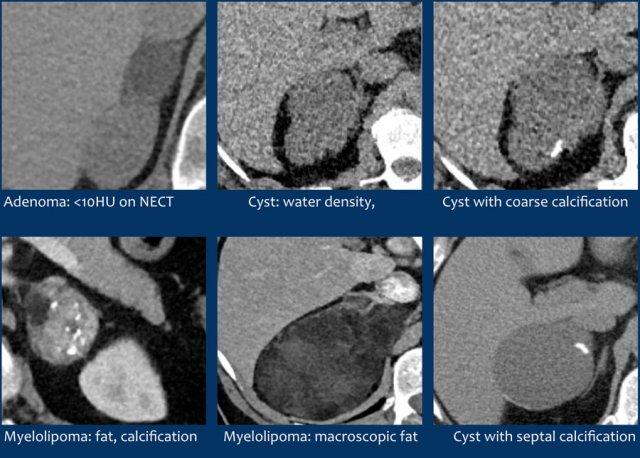

Nhiều tổn thương tuyến thượng thận có thể được phân loại là thường gặp lành tính và không cần theo dõi (bảng):

- U tuyến giàu lipid

- U tủy mỡ (Myelolipoma)

- Nang

- Xuất huyết (có tiền sử phù hợp, ví dụ: chấn thương hoặc bệnh nặng)

- Các tổn thương có vôi hóa lành tính

- Các tổn thương không thay đổi trong thời gian dài (> 6-12 tháng) (+ không có tiền sử ung thư)

- Các tổn thương không ngấm thuốc

Dưới đây là một số ví dụ về các tổn thương thường gặp lành tính.

U tuyến giàu lipid

70% u tuyến chứa nhiều mỡ nội bào và sẽ có tỷ trọng thấp trên CT không tiêm thuốc cản quang [4,5].

Tỷ trọng bằng hoặc dưới 10 HU được coi là tiêu chuẩn chẩn đoán u tuyến giàu lipid.

Nang

Nang đơn thuần là tổn thương bờ rõ, tỷ trọng nước và không ngấm thuốc cản quang.

Nang có thành mỏng và có thể có các vách mỏng.

Các tổn thương có vôi hóa lành tính

Vôi hóa thô, dạng tròn, ngoại vi hoặc theo vách thường gặp trong lành tính và có thể thấy trong:

U tủy mỡ (Myelolipoma)

U tủy mỡ là các khối u lành tính cấu thành từ các thành phần tủy xương.

Thông thường chúng dễ nhận biết trên CT hoặc MRI vì chứa các vùng mỡ đại thể.

Vôi hóa gặp trong 24% các trường hợp.